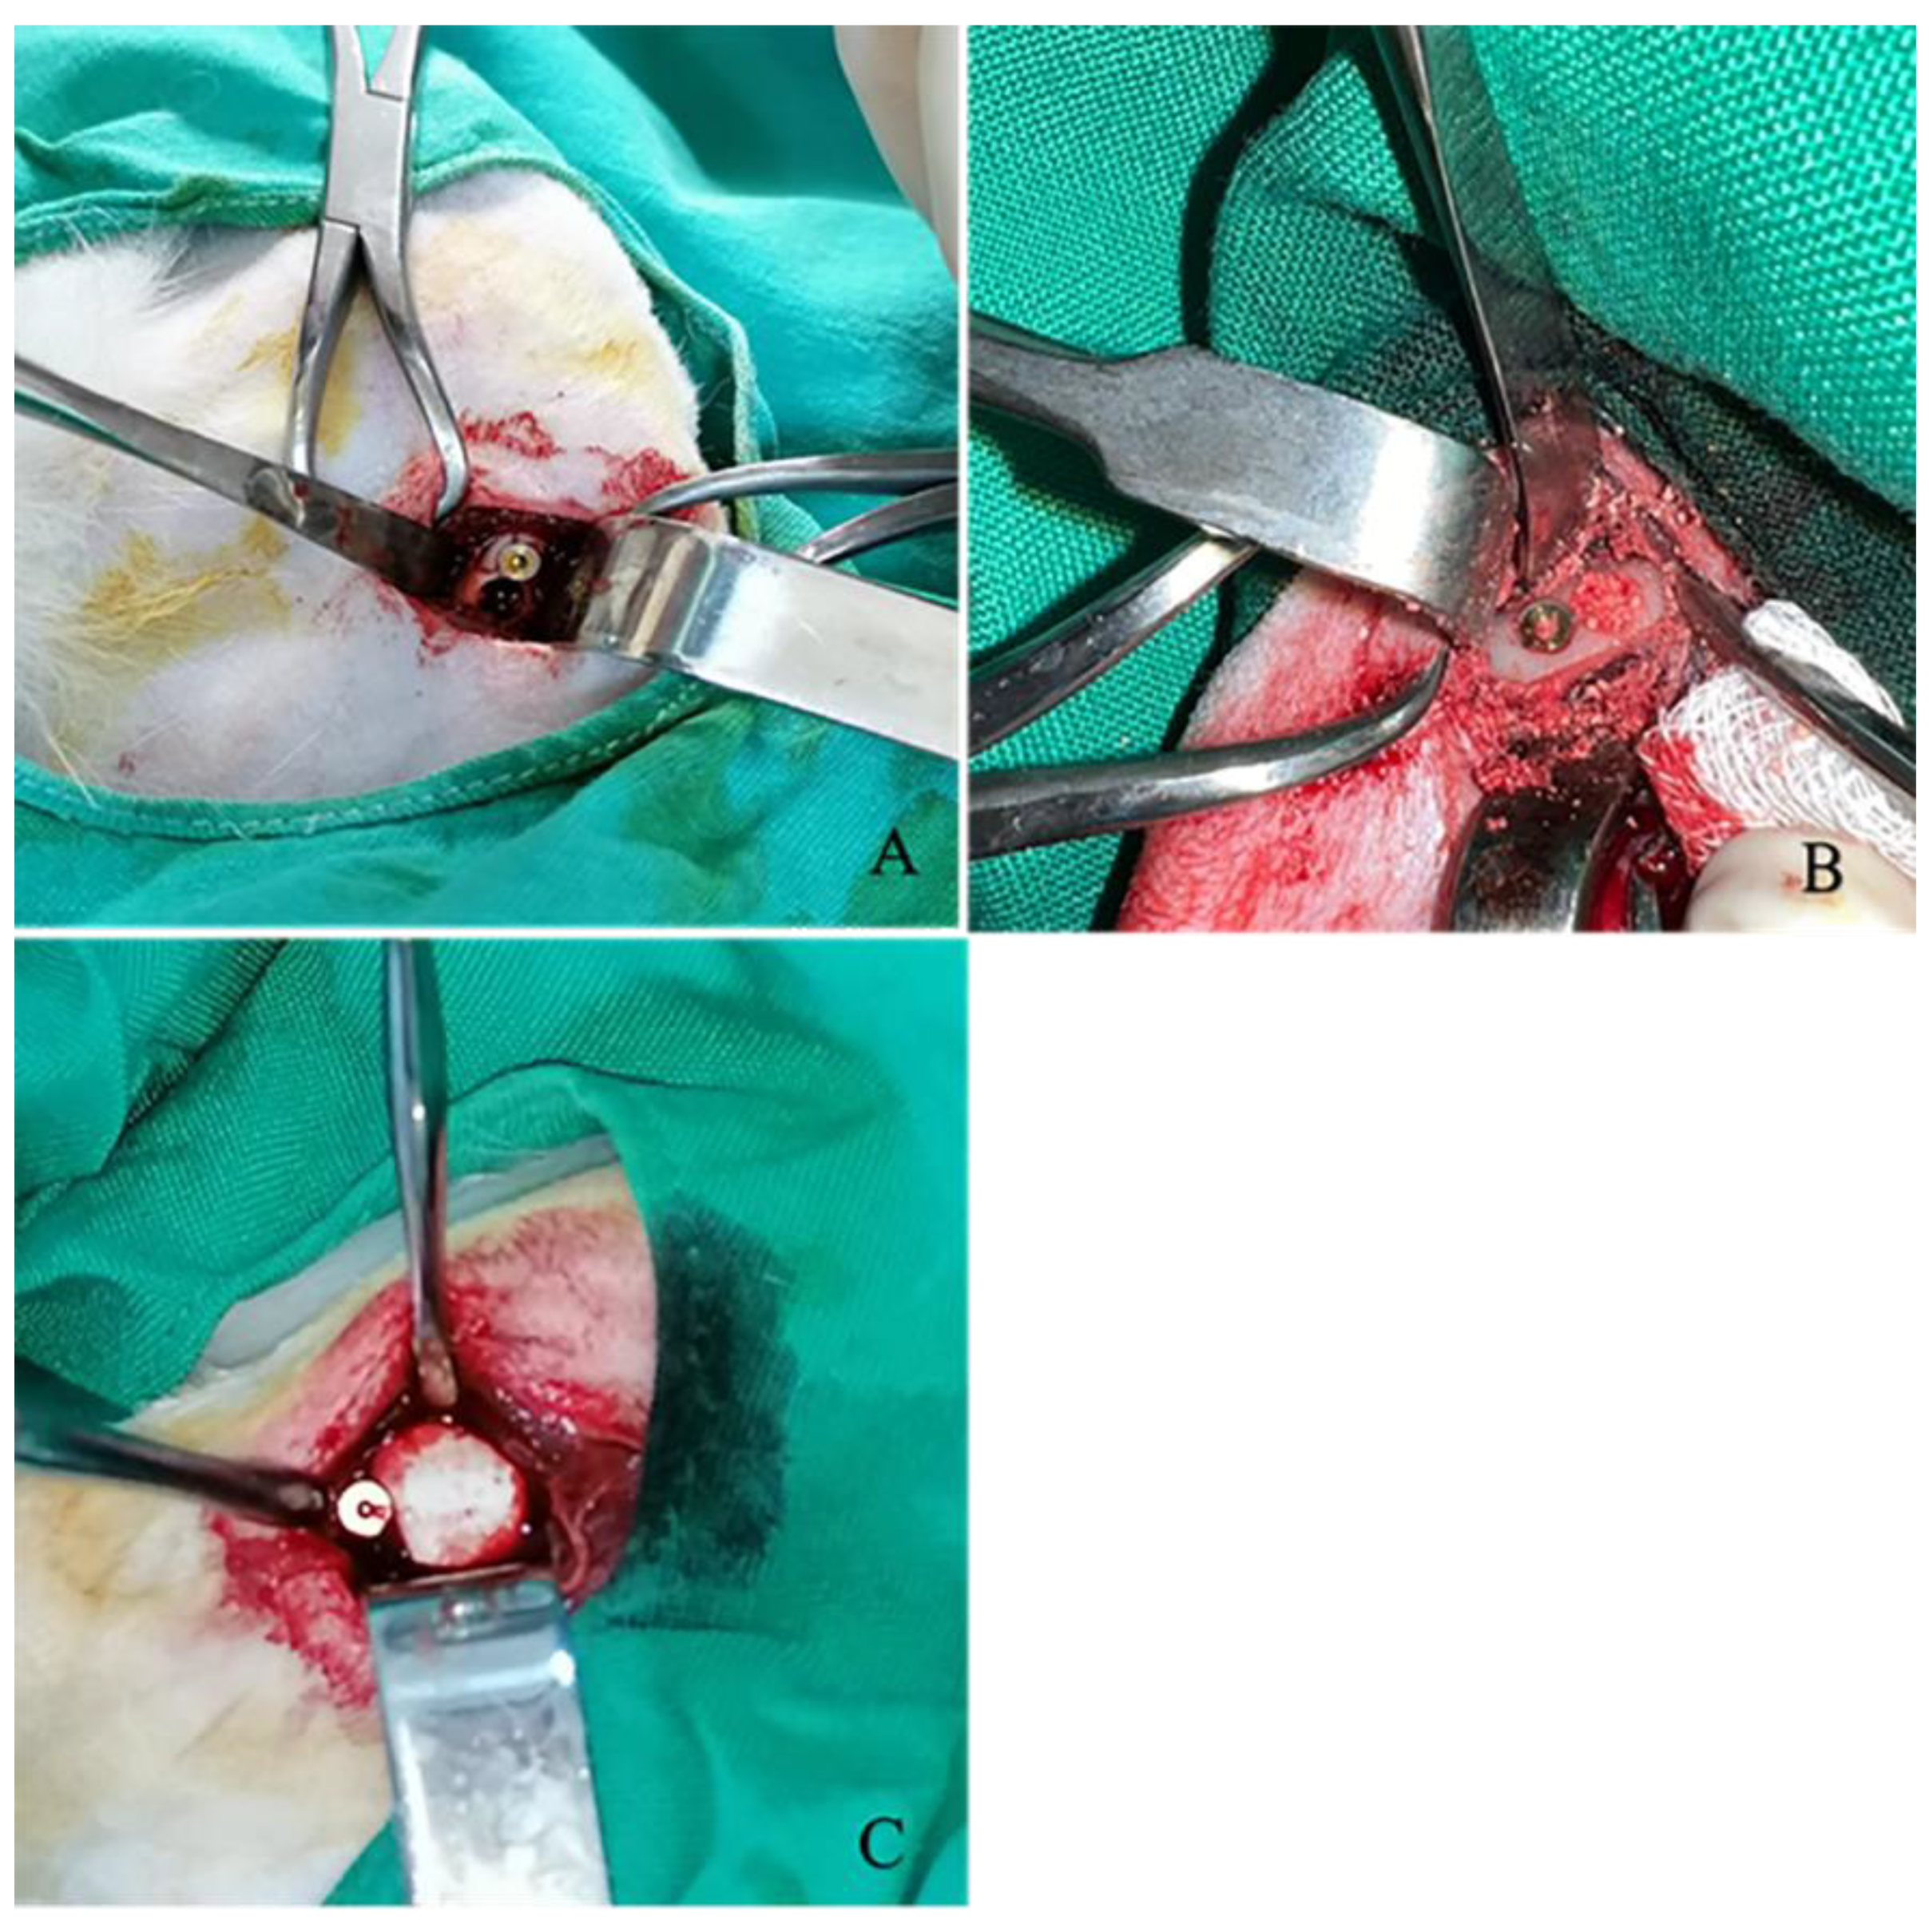

Subsequently, 32 defects were treated with graft applications according to the respective groups and closed with a membrane (Figure 3). Once hemostasis had been achieved, the periosteum and muscles were closed with a 3/0 absorbable multifilament suture following standard surgical procedures. Subsequently, the skin was closed with 3/0 non-absorbable multiflament suture thread. Following the surgical procedure, all animals received intramuscular injections (0.5 mL/kg). The antibiotic Procillin (penicillin G procaine 400,000 IU/mL, Fako, Istanbul, Turkey) was administered. After the surgical procedure, subjects were given ad libitum access to standard rabbit feed and water. The dressings were changed daily, and the healing status of the wounds was observed and recorded. The skin sutures were removed on the tenth day.

Figure 3.

(A) The creation of a 4 mm diameter defect and subsequent implant placement adjacent to the defect. (B) Filling-in of the defects is shown by the relevant group. (C) Closure of all defects with a membrane is shown.